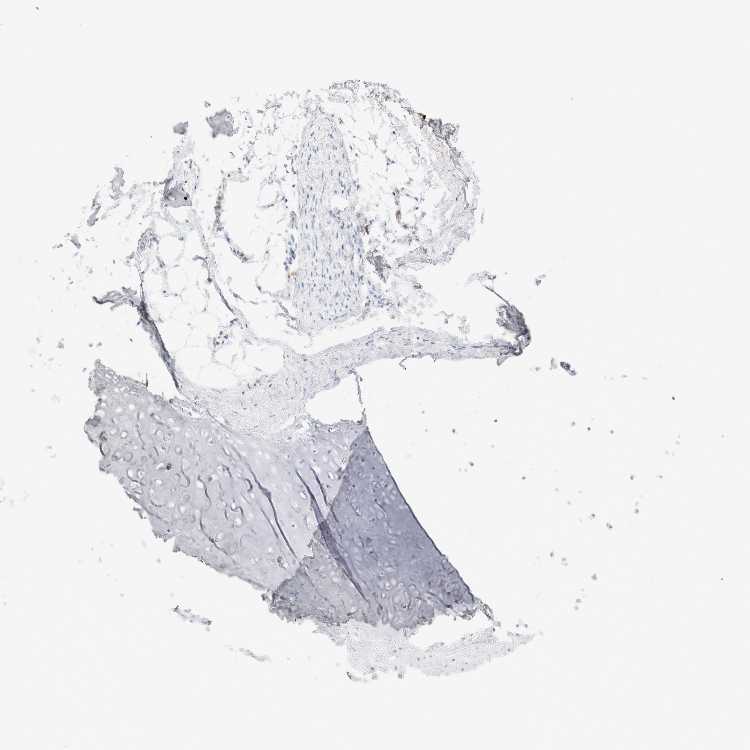

ADIPOSE TISSUE - Antibody stainingi

Antibody staining in the annotated cell types in the current human tissue is reported as not detected, low, medium, or high, based on conventional immunohistochemistry profiling in selected tissues. This score is based on the combination of the staining intensity and fraction of stained cells.

Each image is clickable and will lead to virtual microscopy that enables deeper exploration of all samples and also displays staining intensity scores, fraction scores and subcellular localization as well as patient and tissue information for each sample.

Antibody HPA003595Antibody HPA024006Antibody CAB009434Antibody CAB056159Antibody CAB080011

Adipocytes Not detectedNot detectedLowNot detectedNot detected